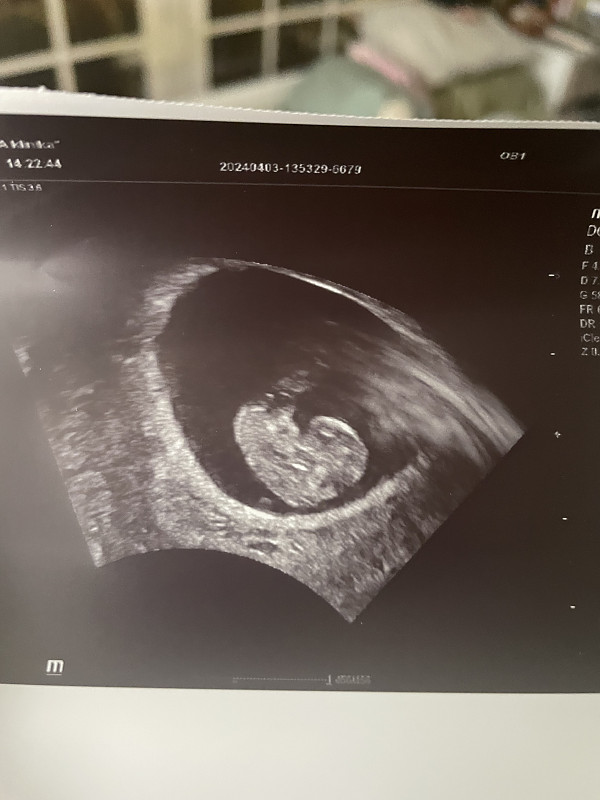

Sveikos. Grįžtu su savo stebuklu! Prieš 2 savaites buvo nustatytas nesivystantis ir laukėm persileidimo. Šiandien nueinu pas gydytoją, kad niekaip neprasideda persileidimas. Pažiūri su echo, o ten širdelė plaka!

Sveikos. Grįžtu su savo stebuklu! Prieš 2 savaites buvo nustatytas nesivystantis ir laukėm persileidimo. Šiandien nueinu pas gydytoją, kad niekaip neprasideda persi…

Apsilankymo metu buvo beveik 10sav.širdelė plaka, sako viskas gerai 🙂